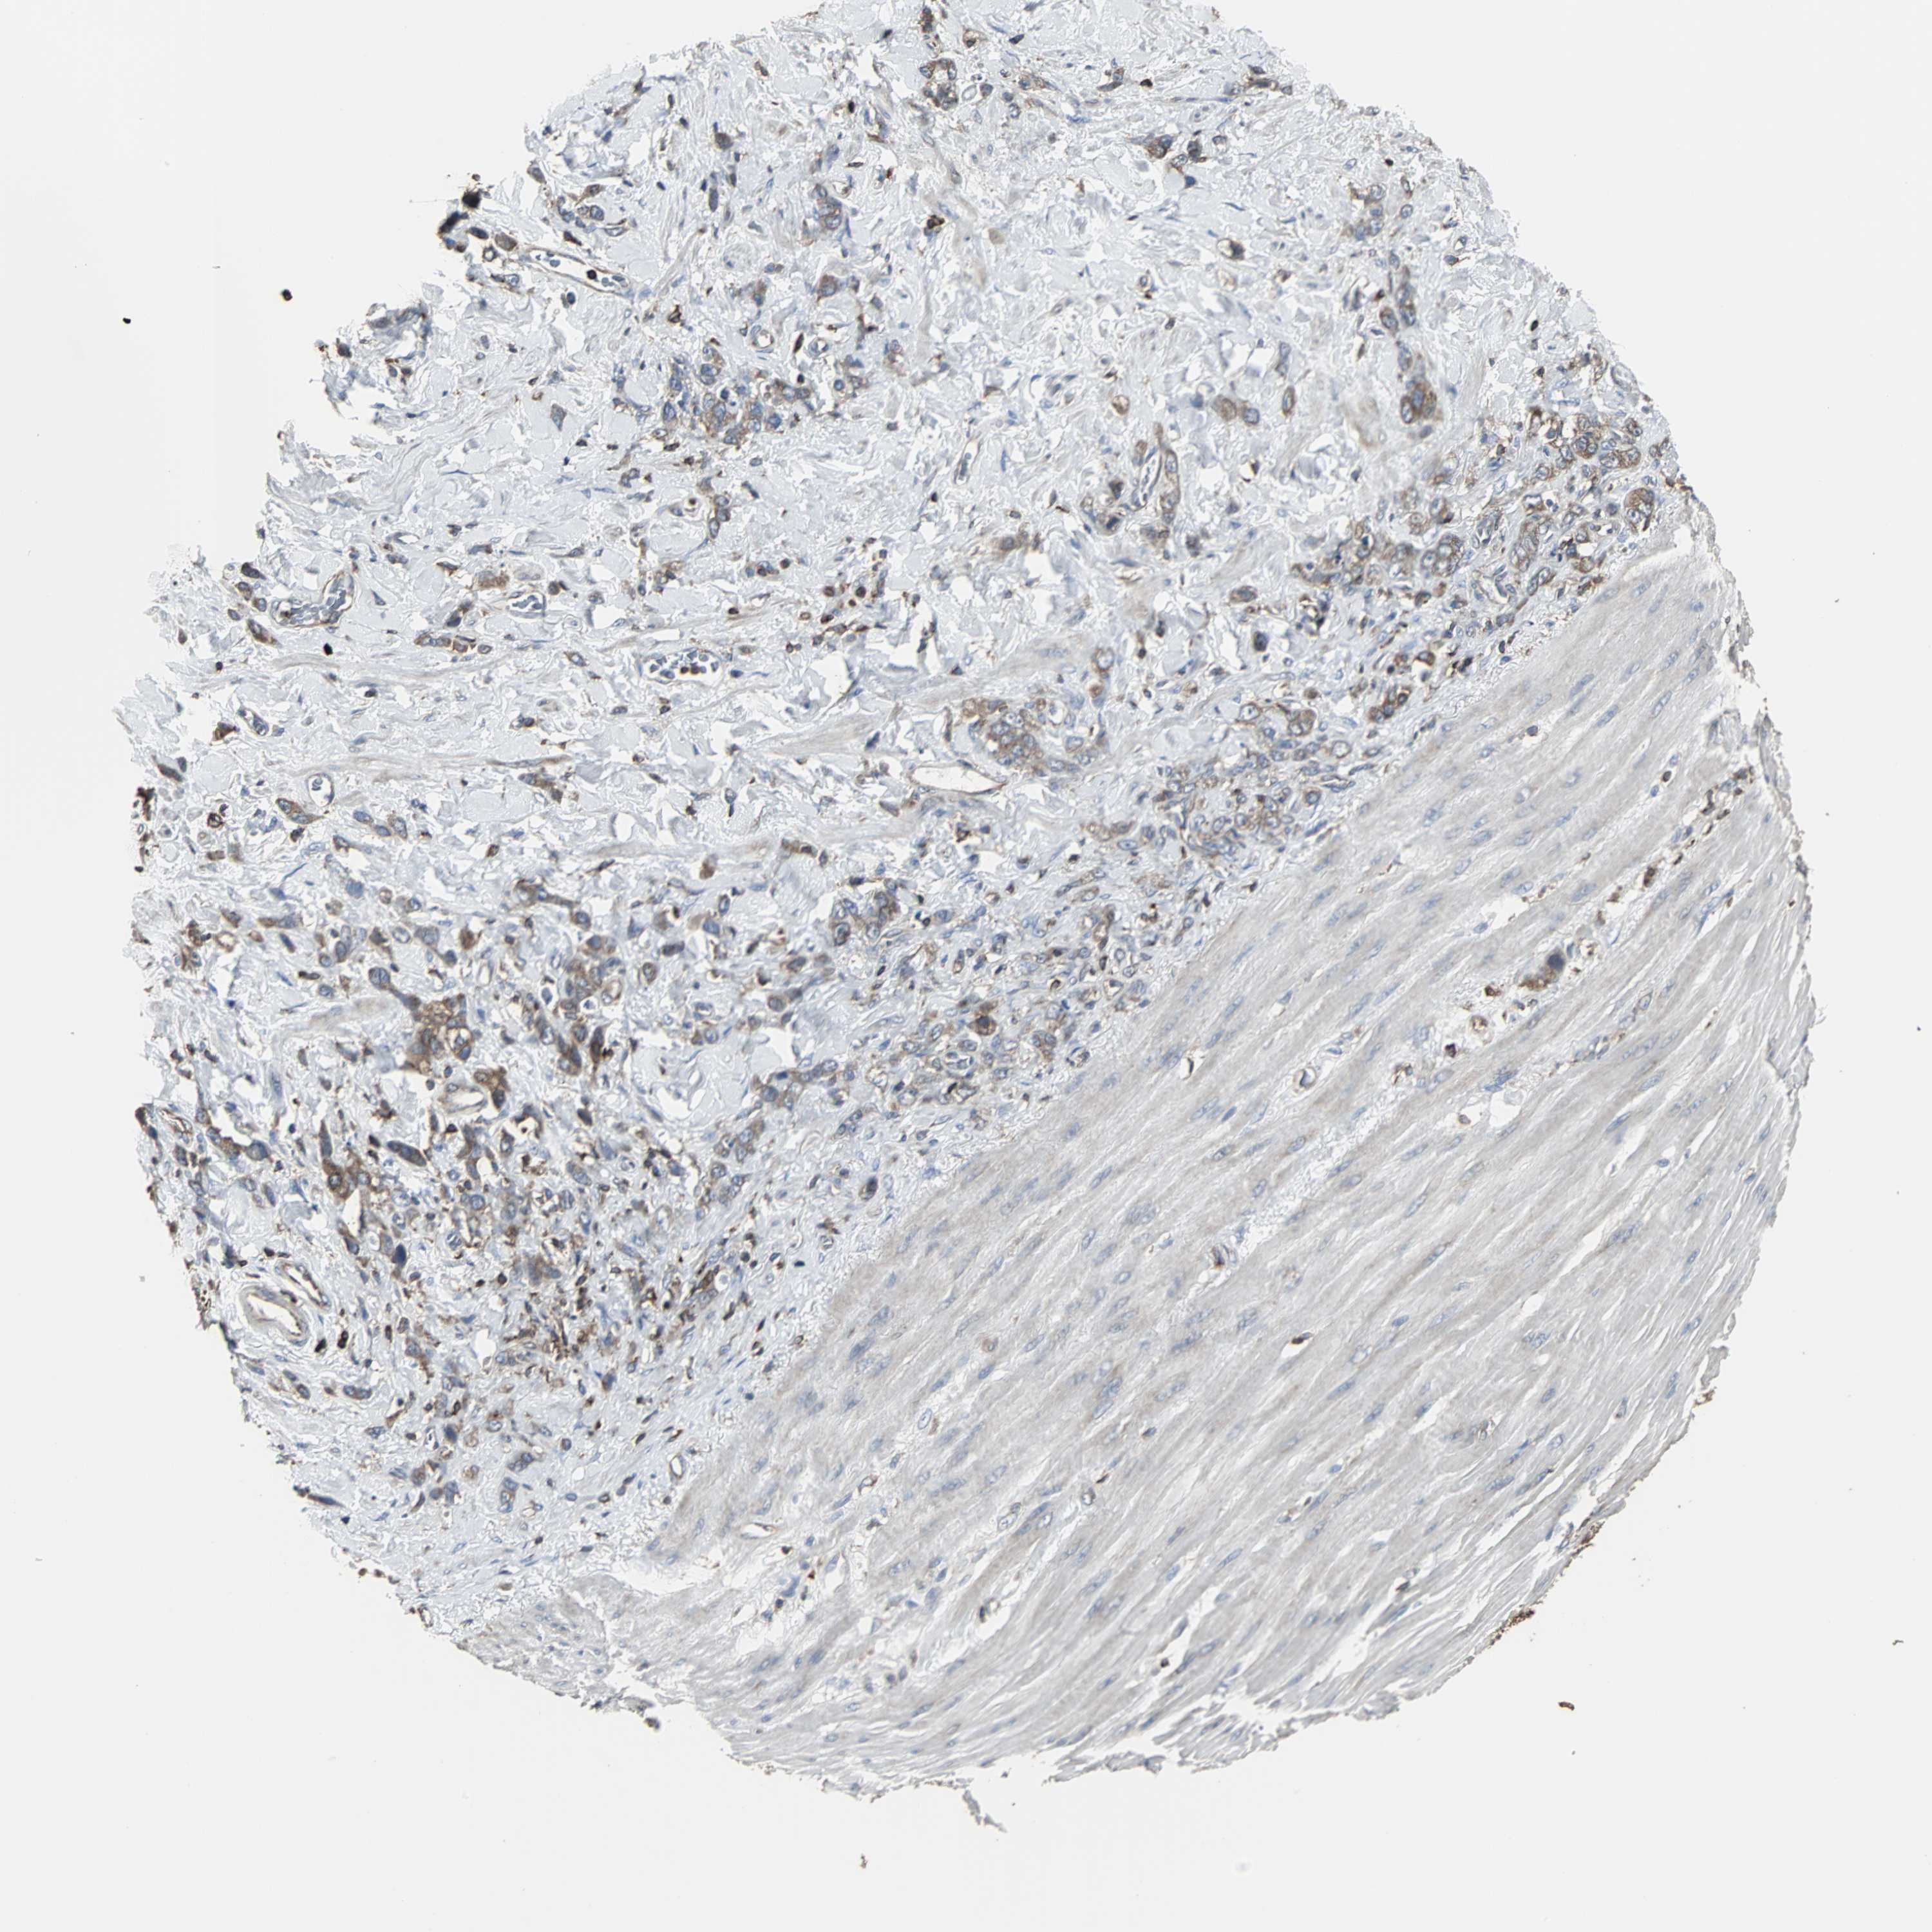

STOMACH CANCER - Protein expressioni

A mouse-over function shows sample information and annotation data. Click on an image to view it in a full screen mode. Samples can be filtered based on level of antibody staining by selecting one or several of the following categories: high, medium, low and not detected. The assay and annotation is described here.

Note that samples used for immunohistochemistry by the Human Protein Atlas do not correspond to samples in the TCGA dataset.

Antibody stainingi

Antibody staining in the annotated cell types in the current human tissue is reported as not detected, low, medium, or high, based on conventional immunohistochemistry profiling in selected tissues. This score is based on the combination of the staining intensity and fraction of stained cells.

Each image is clickable and will lead to virtual microscopy that enables deeper exploration of all samples and also displays staining intensity scores, fraction scores and subcellular localization as well as patient and tissue information for each sample.

Antibody HPA006979

Staining

High

Medium

Low

Not detected

Intensity

Strong

Moderate

Weak

Negative

Quantity

>75%

75%-25%

<25%

None

Location

Nuclear

Cytoplasmic/membranous

Cytoplasmic/membranous,nuclear

Adenocarcinoma, NOS

Adenocarcinoma, High grade